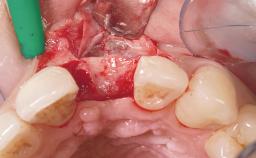

Immediate Flapless Placement of an Implant in a Maxillary Left Central Incisor Site

A 42-year-old female patient was referred to our clinic at the School of Dentistry of the University of São Paulo in November 2004, presenting a deficient restoration in the upper left central incisor. The clinical examination revealed no gingival retraction or any signs of gingival inflammation and, therefore, previous periodontal treatment was not considered. The patient presented a high lip line at full smile and a thin tissue biotype. This combination characterized a high-risk situation from an anatomic point of view, which required careful preoperative planning and cautious surgical execution.

Soft Tissue Anatomy Intact Defective

Bone Volume Horizontally and vertically sufficient Horizontally deficient Deficient vertically or deficient vertically AND horizontally

Loading Protocol Immediate

Provisional Implant-Supported Prosthesis Prosthodontic margin < 3 mm apical to mucosal margin Prosthodontic margin < 3 mm apical to mucosal margin